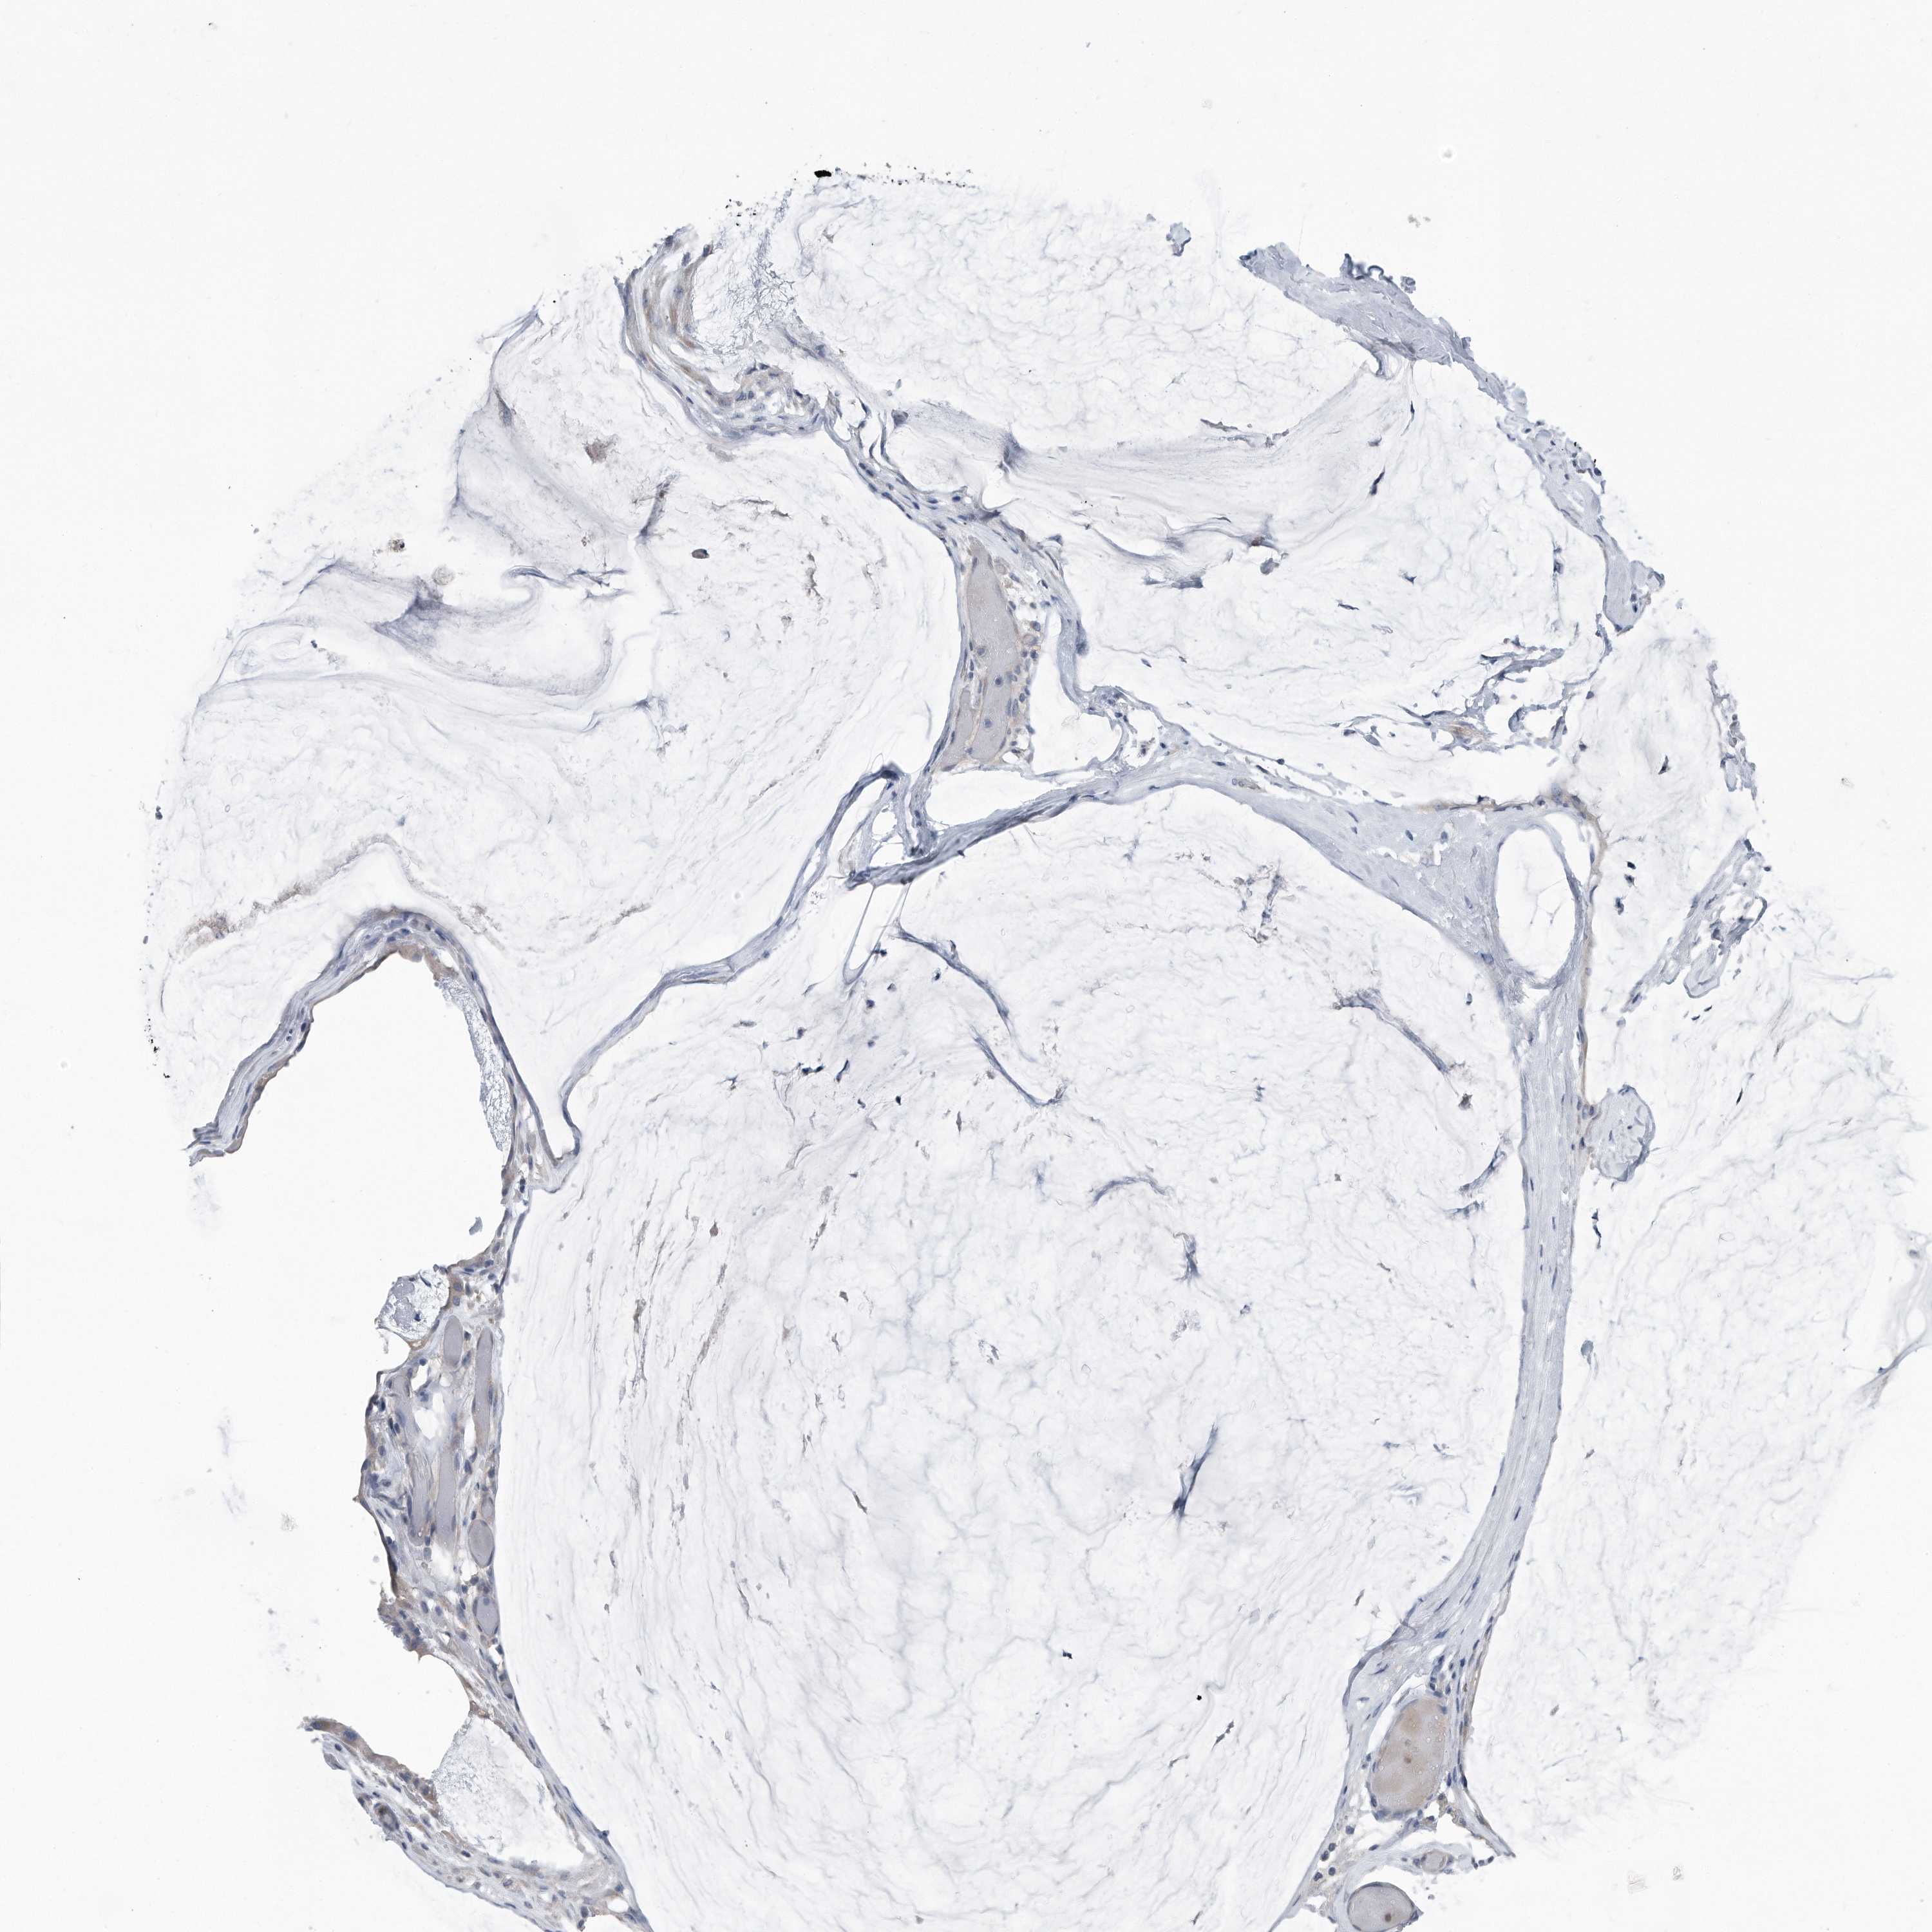

OVARIAN CANCER - Protein expressioni

A mouse-over function shows sample information and annotation data. Click on an image to view it in a full screen mode. Samples can be filtered based on level of antibody staining by selecting one or several of the following categories: high, medium, low and not detected. The assay and annotation is described here.

Note that samples used for immunohistochemistry by the Human Protein Atlas do not correspond to samples in the TCGA dataset.

Antibody stainingi

Antibody staining in the annotated cell types in the current human tissue is reported as not detected, low, medium, or high, based on conventional immunohistochemistry profiling in selected tissues. This score is based on the combination of the staining intensity and fraction of stained cells.

Each image is clickable and will lead to virtual microscopy that enables deeper exploration of all samples and also displays staining intensity scores, fraction scores and subcellular localization as well as patient and tissue information for each sample.

Antibody HPA030147

Staining

High

Medium

Low

Not detected

Intensity

Strong

Moderate

Weak

Negative

Quantity

>75%

75%-25%

<25%

None

Location

Nuclear

Cytoplasmic/membranous

Cytoplasmic/membranous,nuclear

Cystadenocarcinoma, serous, NOS

Carcinoma, endometroid

Cystadenocarcinoma, mucinous, NOS

Carcinoma, NOS